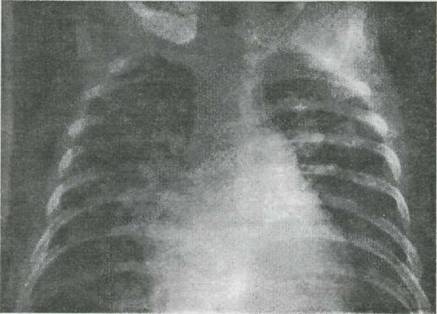

Fig. 9-2, Defect septal ventricular nerestrictiv cu hipertensiune pulmonara. Radiografie cardiopulmcnara; cardiomegalie importanta

bombarea trunchiului arterei pulmonare, congestie vasculara pulmonara

Radiografia cardio-pulmonara demonstreaza cardiomegalia legata de cresterea dimensiunilor ambilor ventriculi si a atriului stāng, dar silueta cardiaca ramāne nesugestiva pentru acest diagnostic. Hipervascularizatia pulmonara este evidenta si frecvent se remarca tulburari de ventilatie, variabile, "mobile", generate de compresiunea vasculara a cailor aeriene si puseelor de suprainfectie bronho-pulmonara divers intricate.